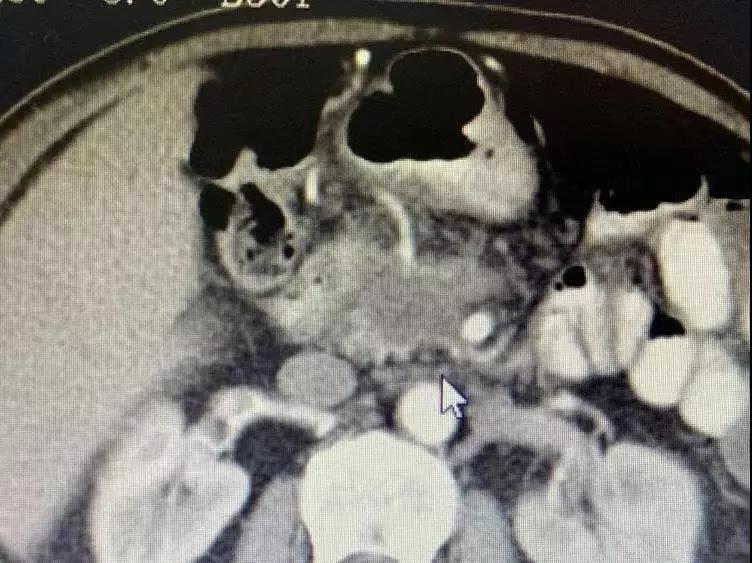

До операции опухоль поджелудочной железы окружает кровеносные сосуды и обнаруживаются метастазы в брюшных лимфатических узлах.

Медсестра сказала мне, что он и его семья были очень добрыми, и они улыбались и кивали вам, когда приветствовали. Было сказано, что он внезапно почувствовал боль в верхней части живота в апреле этого года. Позже в мае он прошел обследование в местной больнице. Неподтвержденная масса в поджелудочной железе размером 3 см была обнаружена вблизи верхней брыжеечной вены, которая предположительно была раком поджелудочной железы. 25 июля у него было еще одно обследование, и его состояние ухудшилось. Опухоль проникла в верхнюю брыжеечную вену и артерию; многочисленные маленькие лимфатические узлы были обнаружены перед полой веной и вблизи аорты. Из-за ограниченных медицинских ресурсов лучшего лечения в Непале не было. Затем его врач порекомендовал ему Онкологическую больницу Фуда.

Необратимая электропорация при опухоли поджелудочной железы

Для дальнейшего лечения как можно скорее его сын привез его в Онкологическую больницу Фуда 31 августа. После обследования ему был поставлен диагноз несоциализированная аденокарцинома III стадии в поджелудочной железе и диабет II типа с множественными узлами в печени, легких и щитовидной железе. После обсуждения с доктором Ню Личжи и медицинской командой он и его семья согласились провести катетеризацию в подключичной вене 6 сентября и на сдедующий день необратимую электропорацию при опухоли поджелудочной железы. После интенсивной терапии его состояние улучшалось с каждым днем.